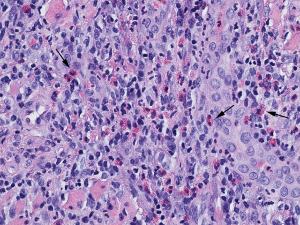

Histopathology reveals dense mixed inflammatory infiltrate of lymphocytes, plasma cells, large mononuclear cells include histiocytes and numerous eosinophils (Figure 3).